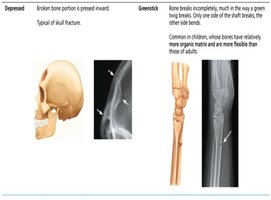

Depressed | Broken bone portion is pressed inward. Typical of skull fracture. |

Greenstick | Bone breaks incompletely, like a green twig. Common in children. |